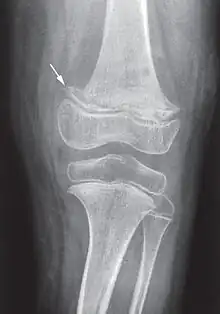

X-ray of the knee joint (arrow indicates scurvy line).

Vitamins are essential to the production and use of enzymes that are involved in ongoing processes throughout the human body.[6] Ascorbic acid is needed for a variety of biosynthetic pathways, by accelerating hydroxylation and amidation reactions. In the synthesis of collagen, ascorbic acid is required as a cofactor for prolyl hydroxylase and lysyl hydroxylase. These two enzymes are responsible for the hydroxylation of the proline and lysine amino acids in collagen. Hydroxyproline and hydroxylysine are important for stabilizing collagen by cross-linking the propeptides in collagen.